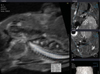

Fig. 6

A. The MR images show the changes during the 4 weeks after irradiation. A modified sagittal view is obtained along the long axis of the incisor. The size and SI of pulp of incisor have decreased (arrow) in Group 2. However, the SI of the MR images in the Group 2 is high at the apex of the incisor from week 2 after irradiation (arrowhead). B. The diagram shows the SI of the pulp tissue versus the time curve. The SI of the irradiated pulp tissue has decreased until week 3 after irradiation. There are differences among the groups at week 3.